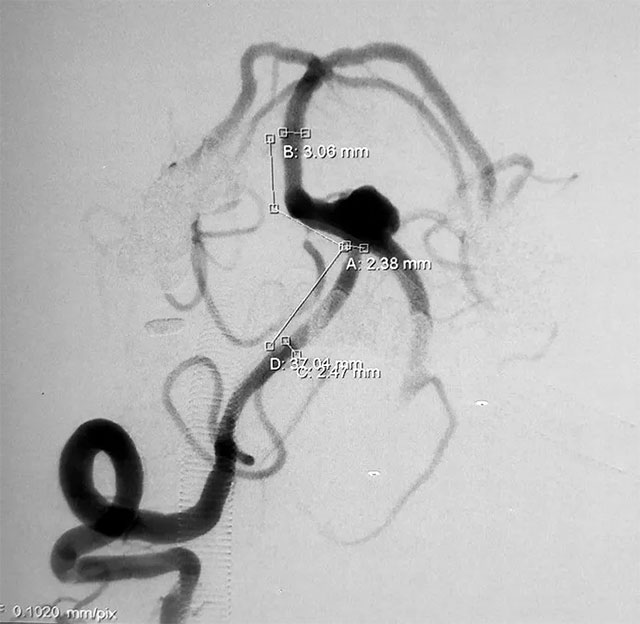

▲ 術(shù)前造影

頭顱CTA顯示:左椎動(dòng)脈多發(fā)狹窄及鈣化,呈串珠樣改變,椎基底動(dòng)脈夾層動(dòng)脈瘤,可見(jiàn)數(shù)枚水泡樣動(dòng)脈瘤;颊呒韧懈哐獕翰∈10余年,兩月前有“頭部外傷史”。血壓檢查,收縮壓153毫米汞柱,舒張壓80毫米汞柱,神志清醒,口角右歪。

張琪博士指出,該患者所患顱內(nèi)夾層動(dòng)脈瘤影像上屬于經(jīng)典型(I型),且動(dòng)脈瘤已破裂出現(xiàn)急性蛛網(wǎng)膜下腔出血,導(dǎo)致頭暈、頭痛、惡心等癥狀,病情兇險(xiǎn),再出血的風(fēng)險(xiǎn)極大,應(yīng)及時(shí)手術(shù)治療。

并且患者血管條件非常差,DSA造影顯示左側(cè)椎動(dòng)脈遠(yuǎn)端近基底動(dòng)脈連接處夾層動(dòng)脈瘤,伴子瘤,術(shù)中很容易破,并且左側(cè)椎動(dòng)脈閉塞,需要先進(jìn)性開(kāi)通,這些無(wú)疑增加了手術(shù)難度。